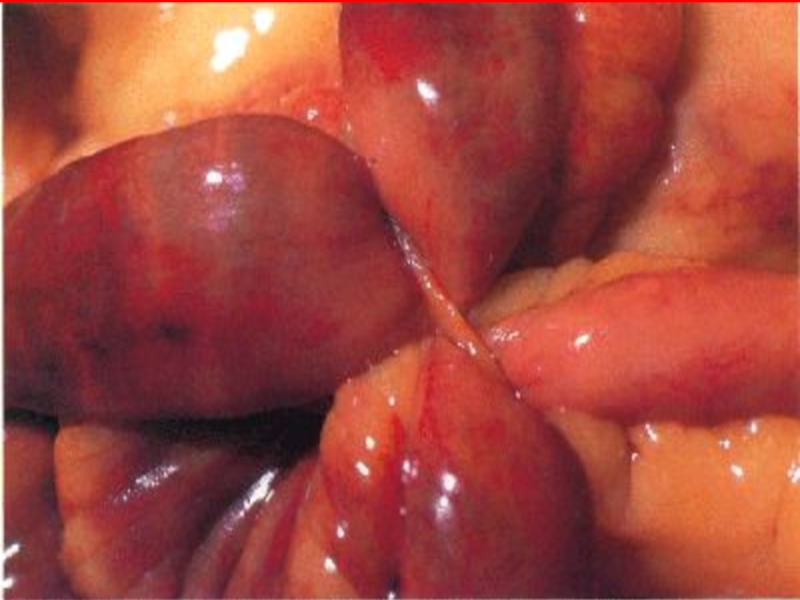

Слайд 14Странгуляционная

Нарушение крово- и лимфо-обращения, иннервации

Слайд 15Странгуляционная

Поражение брыжейки кишки

Включение ишемического компонента

Слайд 18Странгу-

ляция

Узло-

обра-

зование

Ущемление

внутренней

грыжи

наружной

Слайд 21Заворот

Тонкой

кишки

Ободочной

Желудка

Слепой

Сигмовидной

Слайд 24Обтурационная

кишечная

непроходимость

Спаечные пере-гибы кишки (двустволки)

Опухоль тонкой

кишки (саркома)

Рубцо-вые стенозы кишки

Сдавление опухолью, кистой

Опухоль

толстой кишки (рак)

Слайд 27Обтурационная

инородные

тела, безоары

кольцевидная поджелудочная железа

Желч-ные камни

Каловые камни

Гельминты

Слайд 28 Смешанная

Инва-гина-   ция

Спаеч-ная

пороки

развития

Незавер-

шенный

поворот

Удвое-

ние

Мекке-

лев

дивер-

тикул

Слайд 31КЛИНИКА ИНВАГИНАЦИИ

1) все признаки ОКН (квадрат симпто-мов)

2) «пальпация инваги-

ната»

(колбасовидное

образование, чаще в об-

ласти илеоцекального

угла);

3) при пальцевом рек-

тальном исследовании

обнаруживают расши-

ренную ампулу прямой кишки и сле-

ды крови, при толстокишечной инва-гинации - головку инвагината.